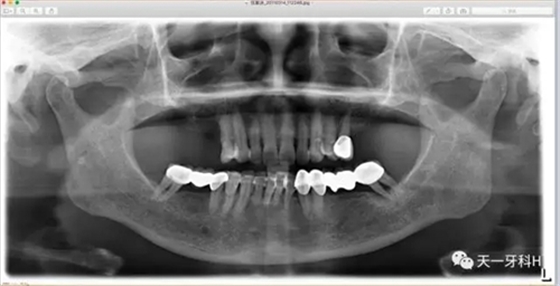

該患者2004年3月16日來(lái)本診所就醫(yī),這張曲面斷層片就是當(dāng)時(shí)拍的,患者之前在外院后牙區(qū)全部做了烤瓷連橋,從這張曲面斷層片上看:右上七牙槽骨已經(jīng)破壞到了根尖,右上五也出現(xiàn)了牙周膜間隙增寬,左上后牙的烤瓷橋的基牙也開(kāi)始出現(xiàn)問(wèn)題了,我常常講:牙周病患者盡量不要做烤瓷牙,很多患者不理解,我用事實(shí)說(shuō)話:這個(gè)牙周病患者就是一個(gè)烤瓷牙的受害者,四個(gè)后牙區(qū)全部做了烤瓷橋!17已經(jīng)牙槽骨破壞到達(dá)了根尖區(qū),15、25、28已經(jīng)開(kāi)始了牙槽骨破壞,我當(dāng)時(shí)勸她拆除烤瓷橋,她不聽(tīng)我的話,我只好拍片記錄下來(lái)她的現(xiàn)狀,下面就是她當(dāng)時(shí)的牙片: